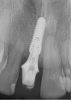

Fig 16. Preoperative periapical radiograph on the day of surgery.

Figure 16

A 23-year-old man reported to the dental practice on January 3. Apparently, while on vacation and celebrating the New Year, the patient experienced a loss of equilibrium and found himself horizontal in the crosswalk. When surveying the damages, his friends noticed he was missing tooth No. 8. Those who were involved were not able to find the missing maxillary central incisor. The young man was eventually seen about 3 days after the trauma. A CBCT radiograph, study models, and photographs were collected, and teeth Nos. 6 through 10 were immobilized with composite and 20 x 20 orthodontic wire (Figure 14). The CBCT and photos were emailed to the dental laboratory, and the analog intraoral impression with a centric occlusion bite registration was sent via ground transportation. Due to the nature of the trauma, the laboratory and the author expeditiously converted the analog diagnostics and merged all the patient's data sets to develop the plan. Based on the 3D data sets, the laboratory and the dentist were able to accurately assess the volume of bone and soft tissue remaining after the trauma. The volume was still intact and soft tissue was plentiful (Figure 15 and Figure 16).

The decision was to develop a surgical guide, place the implant, and fabricate a screw-retained one-piece non-engaging abutment with a slender emergence profile and a polymethyl methacrylate (PMMA) provisional. Ten days after the trauma, the patient was seen in the dental office for the placement of the dental implant. On the day of surgery, a 3D-printed surgical guide was used, developed from the CBCT radiograph and the digitized impressions (Figure 17 and Figure 18).